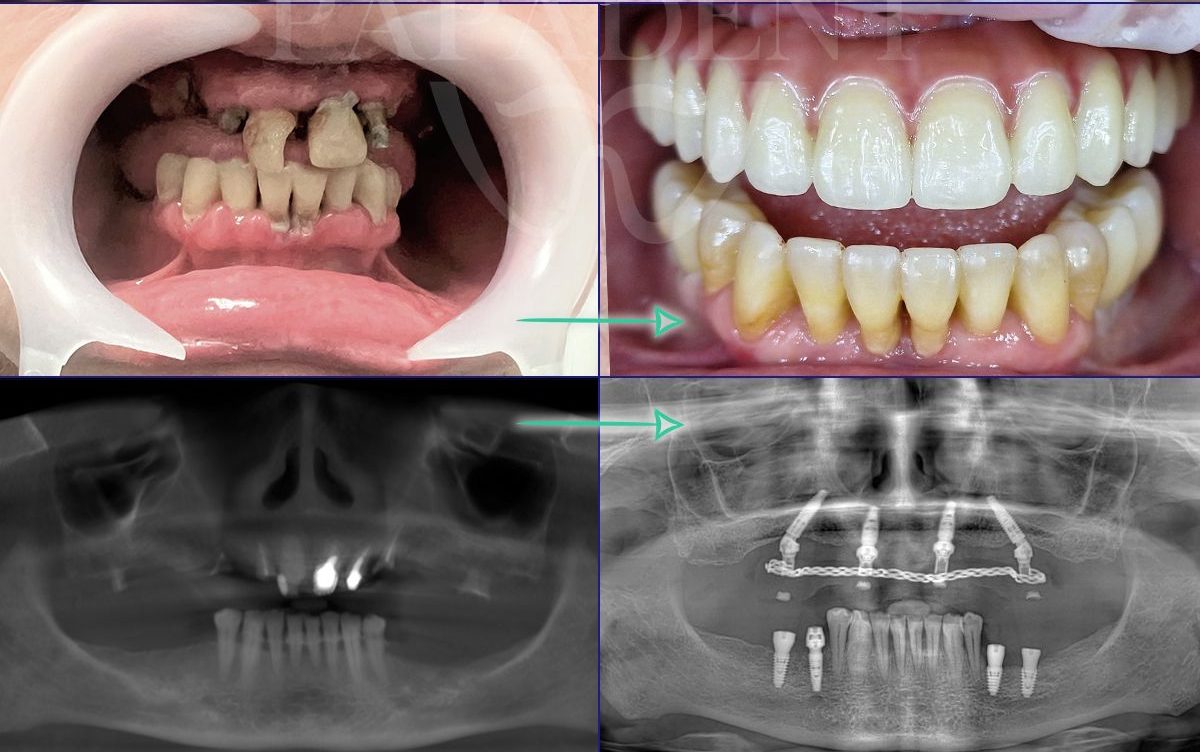

„All-on-4“ yra pažangi dantų implantavimo technika, leidžianti atkurti visą viršutinio arba apatinio žandikaulio dantų lanką vos su 4 implantais. Ant šių implantų fiksuojamas nuolatinis dantų protezas, kuris užtikrina ne tik estetišką šypseną, bet ir pilnavertę kramtymo funkciją. Šis metodas yra greitas, komfortiškas ir daugelio specialistų pripažįstamas kaip vienas efektyviausių sprendimų bedančiams žandikauliams netekus daugelio ar visų dantų.

- Dantų protezai ant 4 implantų vos per 24 – 48 val. Ir turite naujus visus dantis!